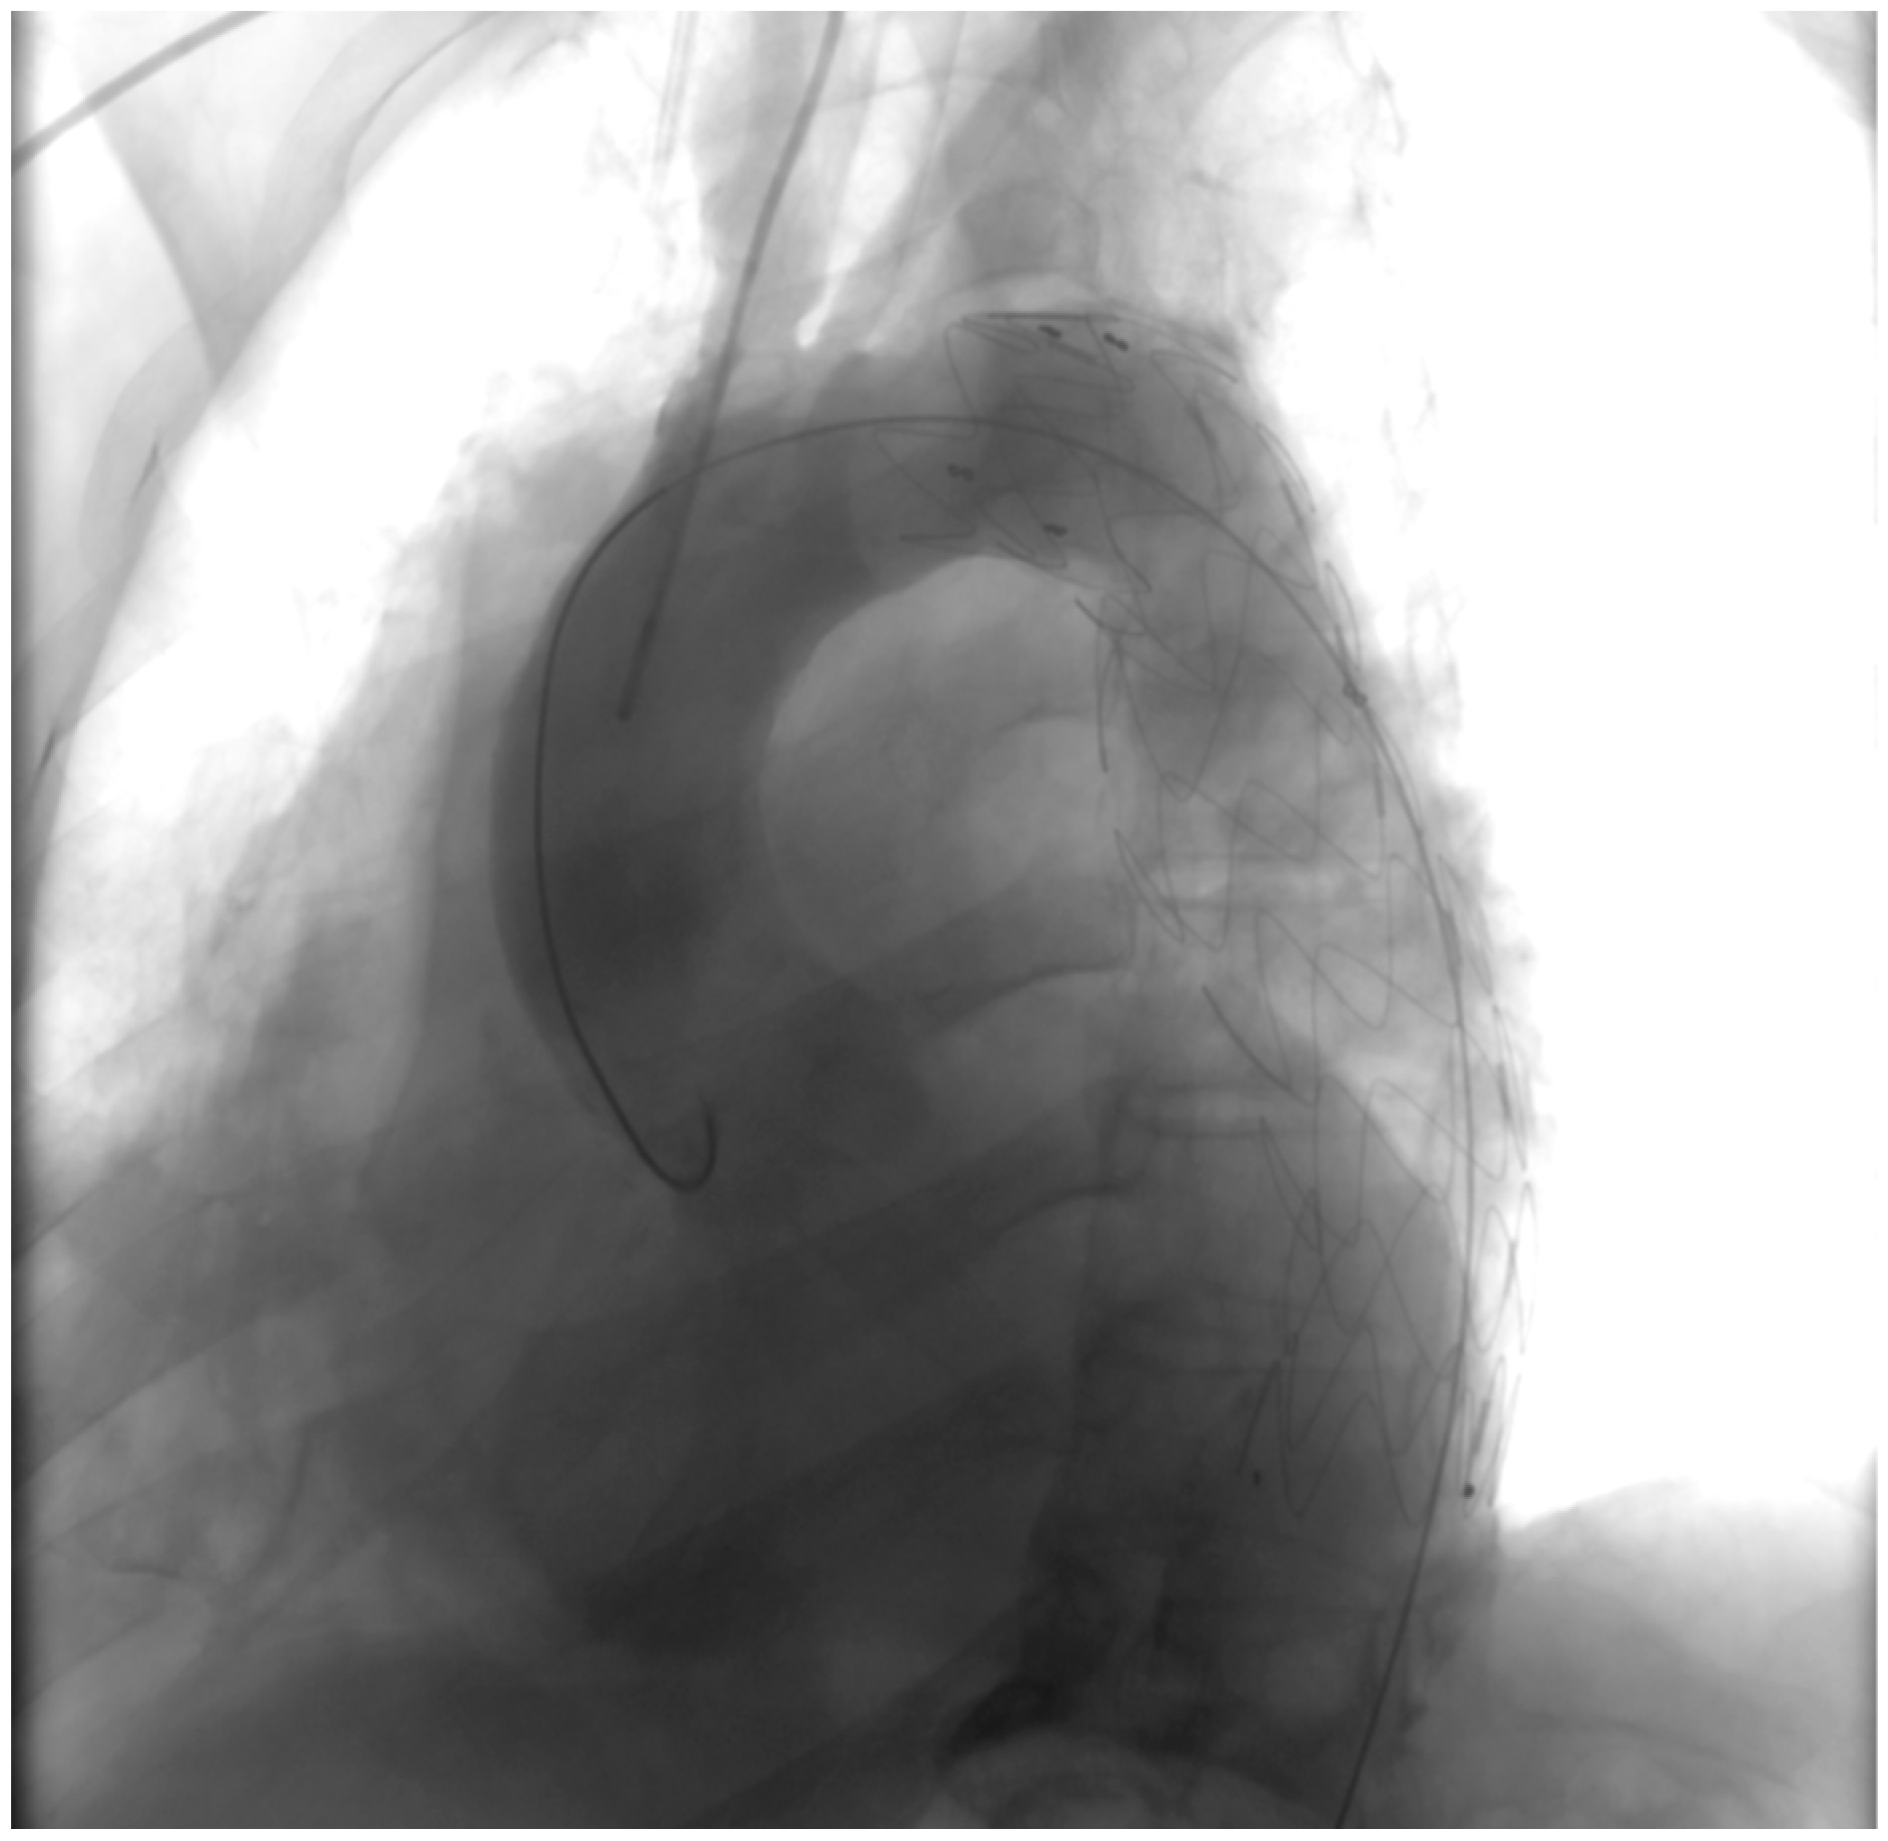

- Penetrating aortic ulcer ruptured: As seen in Figure 2, the thoracic angio-CT scan identified a penetrating ulcer within the aortic wall, particularly located in the isthmic region, measuring approximately 4.2 cm × 3.5 cm. This was a concealed source of significant concern, as it posed an imminent risk of catastrophic hemorrhage.

- Right pleural aortic false aneurysm (Figure 3): The most striking feature was the presence of an expansive false aneurysm within the right pleural cavity, measuring approximately 12.92 cm × 9.3 cm. The size and location of this pseudoaneurysm were unprecedented, introducing a challenge in terms of diagnosis and intervention.